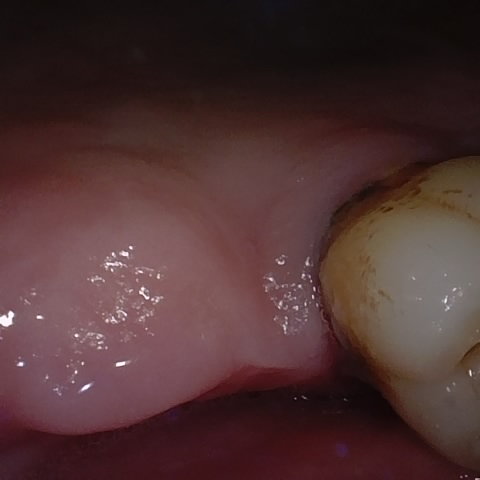

Annotated as "Good"